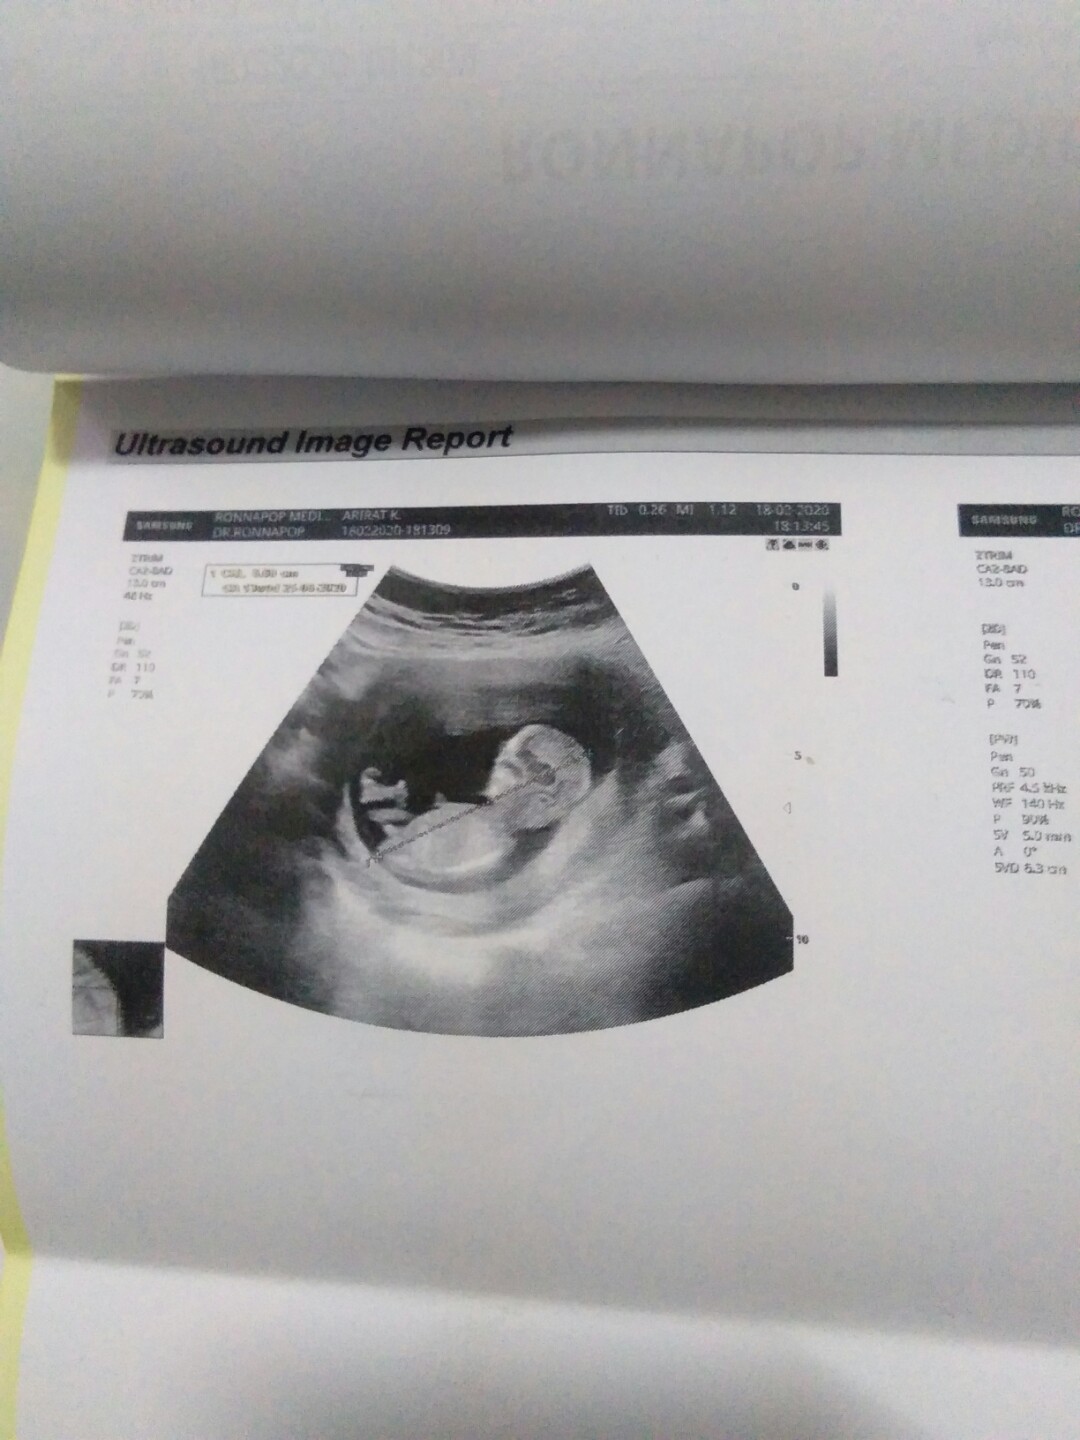

บ้านนี้ตอน12w2dค่ะ

บ้านนี้ตอน12wค่ะ

ซาวด์ตอน 12 w ค่ะ